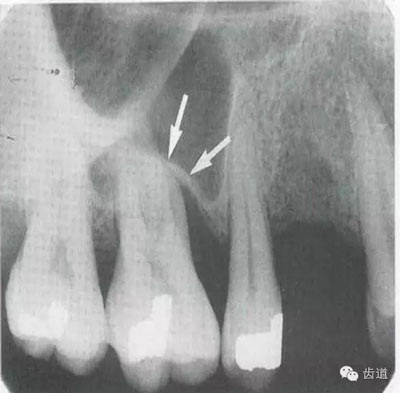

2)營養(yǎng)管:

常見于下頜前牙區(qū),在牙根之間的牙槽骨內(nèi)并與牙長軸平行的密度低的條狀影像。此為小血管進入牙槽突的影像。

3)頦孔:

位于前磨牙根尖區(qū)域,為一大致圓形密度低的影像。頦孔位置變異大,多位于第二前磨牙根尖稍下,注意與根尖周病變區(qū)別,其要點是牙周膜及其骨硬板是否連續(xù)不斷。